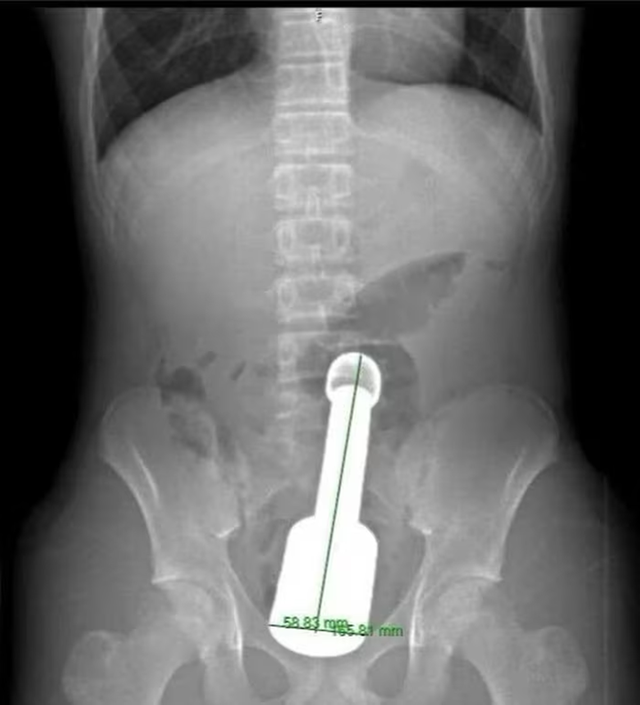

Bệnh nhân nhập viện trong tình trạng đau tức dữ dội vùng hạ vị. Sau khi thăm khám, kết quả chẩn đoán hình ảnh cho thấy một dị vật kim loại lớn mắc kẹt sâu trong trực tràng, gây chèn ép các cơ quan vùng chậu. Đây là tình huống nguy hiểm, dễ dẫn đến biến chứng nặng nếu không xử trí kịp thời.

Hình ảnh chụp X-quang và dị vật được lấy ra khỏi hậu môn của bệnh nhân - Ảnh: BVCC

Theo các bác sĩ, dị vật được xác định là một chiếc chày dài khoảng 18cm, đường kính 6cm. Thách thức lớn nhất đối với ê-kíp là kích thước dị vật khá lớn, đồng thời bị hút chặt bên trong do hiện tượng giống “hiệu ứng chân không”, khiến việc lấy ra gặp nhiều khó khăn.

Sau khoảng 45 phút, dị vật đã được lấy ra an toàn. Khu vực tổn thương chỉ bị xây xát nhẹ và chức năng cơ thắt được bảo tồn.